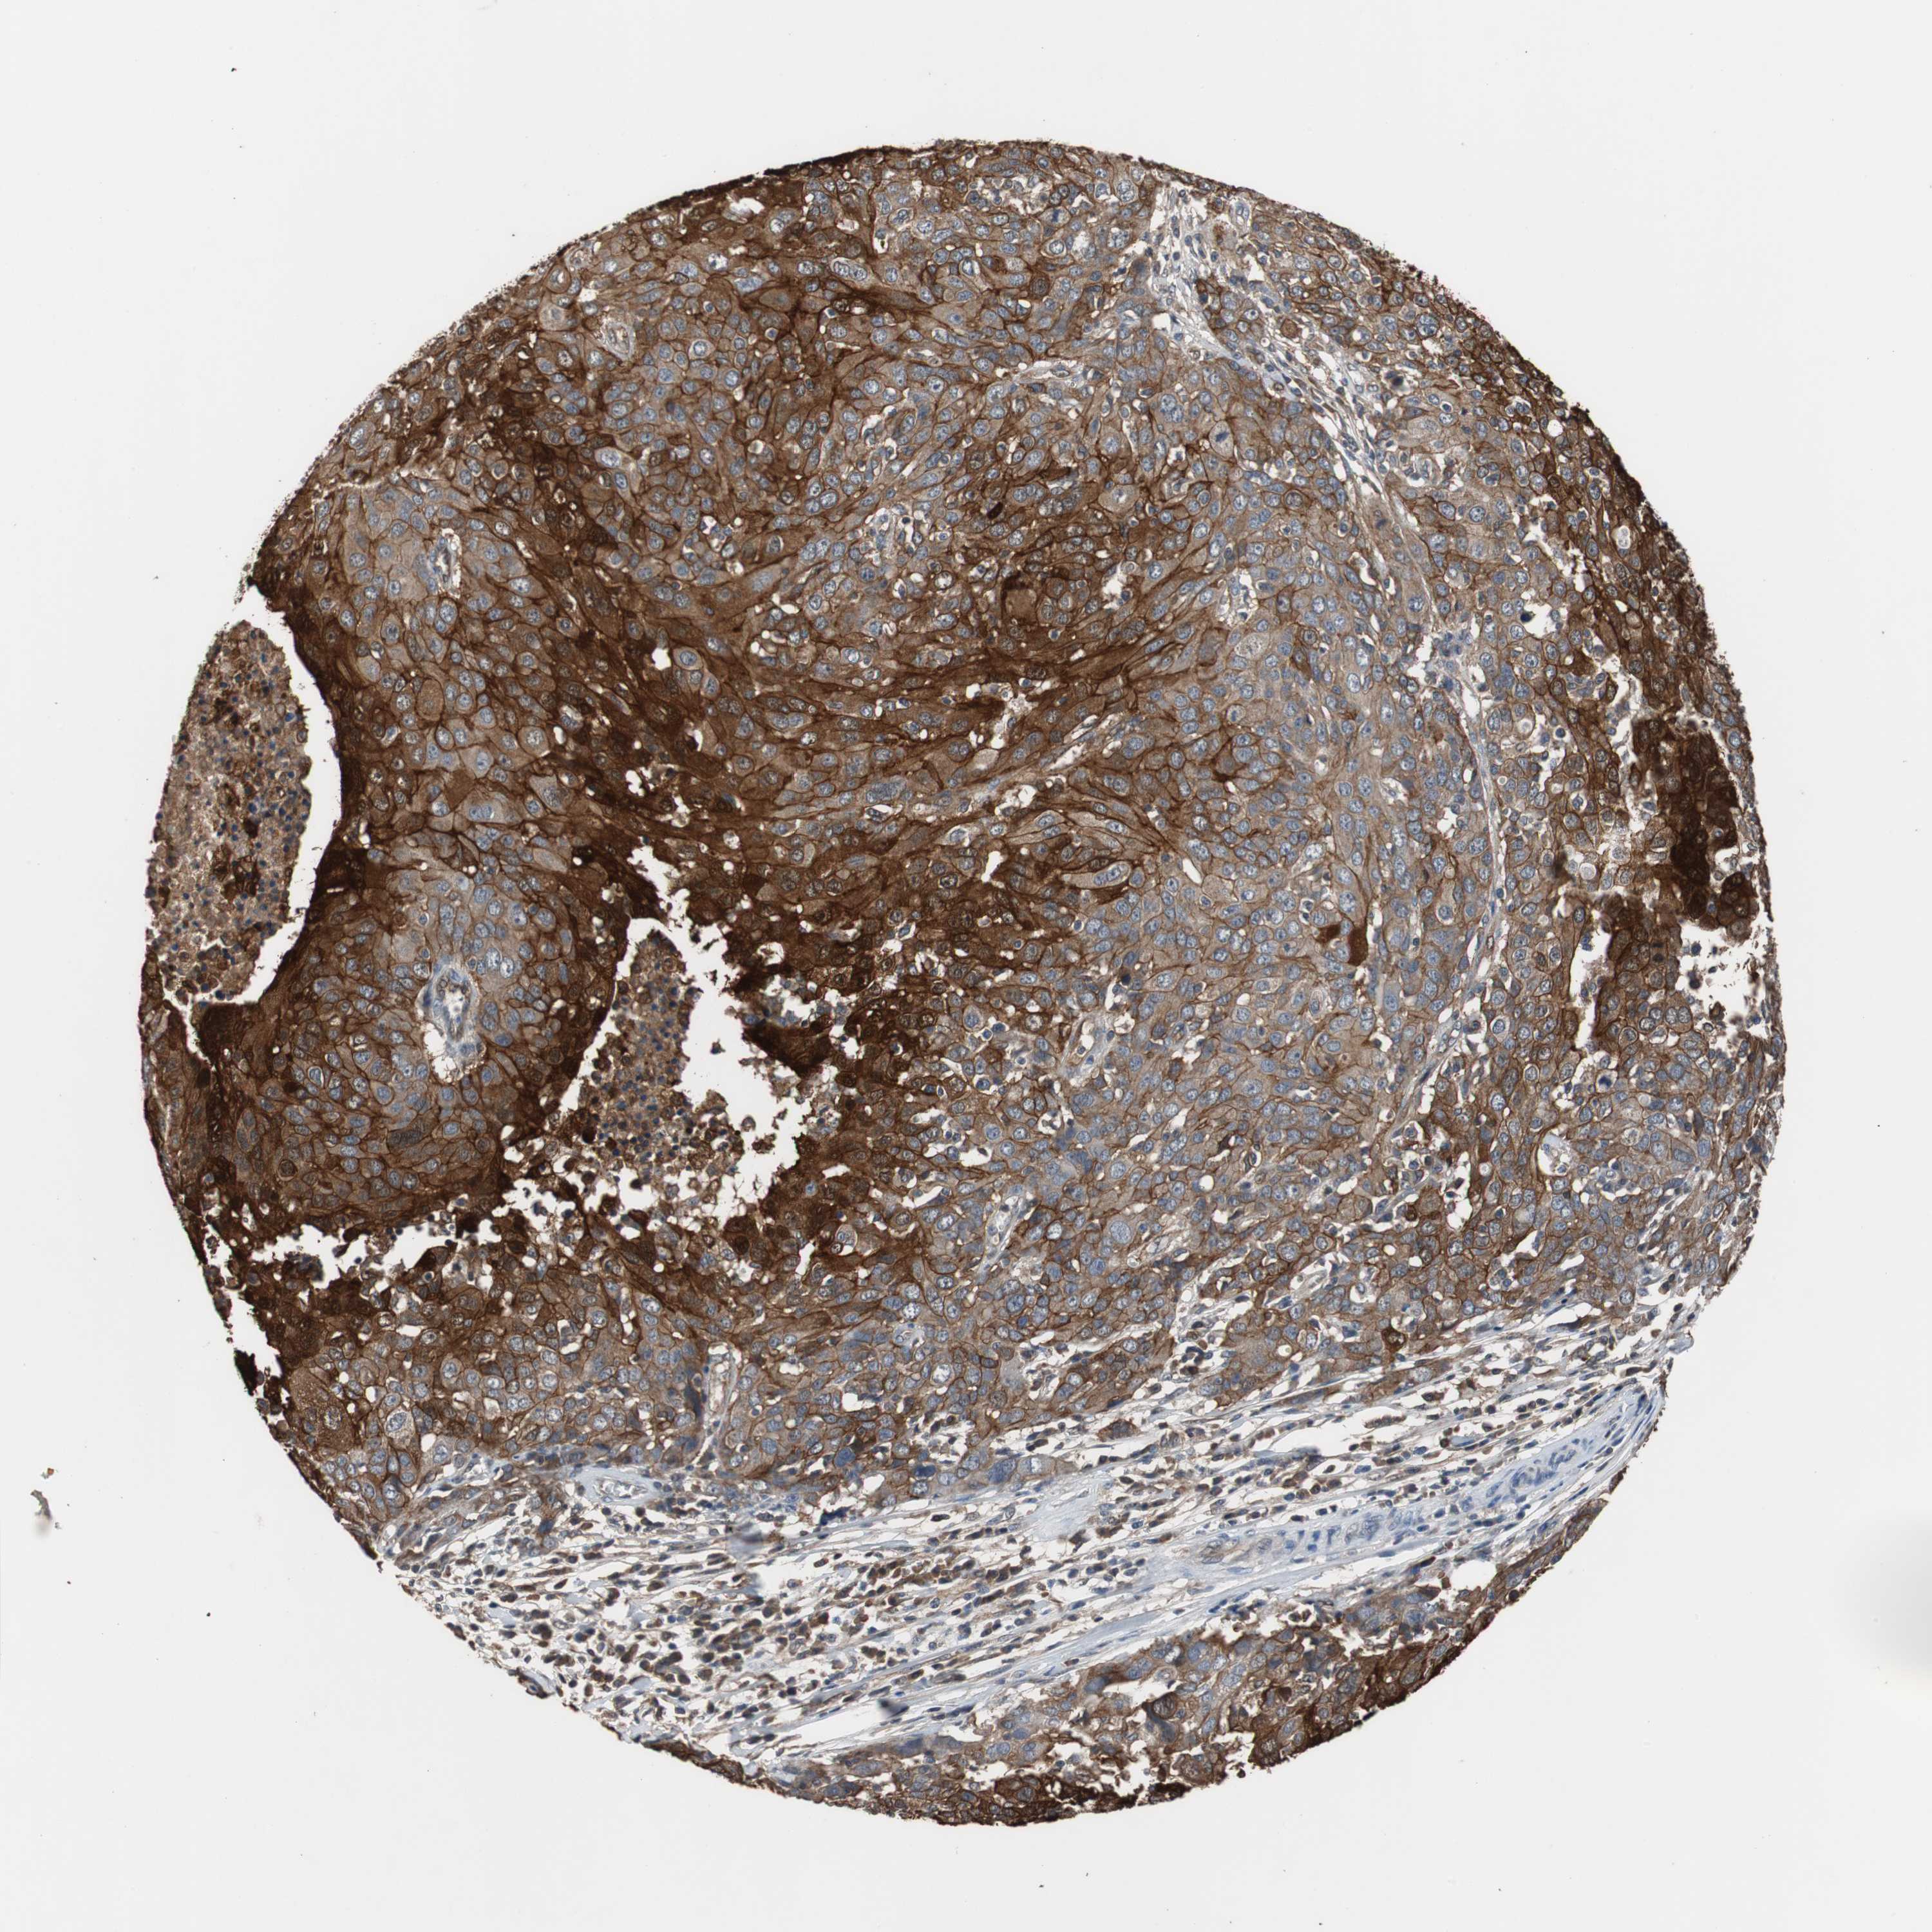

OVARIAN CANCER - Protein expressioni

A mouse-over function shows sample information and annotation data. Click on an image to view it in a full screen mode. Samples can be filtered based on level of antibody staining by selecting one or several of the following categories: high, medium, low and not detected. The assay and annotation is described here.

Note that samples used for immunohistochemistry by the Human Protein Atlas do not correspond to samples in the TCGA dataset.

Antibody stainingi

Antibody staining in the annotated cell types in the current human tissue is reported as not detected, low, medium, or high, based on conventional immunohistochemistry profiling in selected tissues. This score is based on the combination of the staining intensity and fraction of stained cells.

Each image is clickable and will lead to virtual microscopy that enables deeper exploration of all samples and also displays staining intensity scores, fraction scores and subcellular localization as well as patient and tissue information for each sample.

Antibody HPA006881

Staining

High

Medium

Low

Not detected

Intensity

Strong

Moderate

Weak

Negative

Quantity

>75%

75%-25%

<25%

None

Location

Nuclear

Cytoplasmic/membranous

Cytoplasmic/membranous,nuclear

Cystadenocarcinoma, serous, NOS

Cystadenocarcinoma, mucinous, NOS

Carcinoma, endometroid